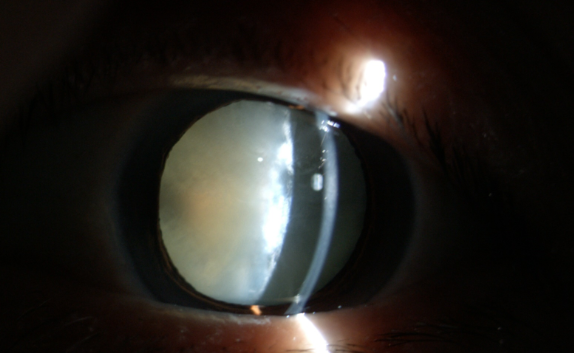

糖尿病為什么更易得白內(nèi)障

【文章導讀】在臨床中,很多糖尿病患者不太重視診治,尤其忽視糖尿病導致的多種眼科并發(fā)癥,如白內(nèi)障。糖尿病友得白內(nèi)障較普通人來說有三個特點:

在臨床中,很多糖尿病患者不太重視診治,尤其忽視糖尿病導致的多種眼科并發(fā)癥,如白內(nèi)障。糖尿病友得白內(nèi)障較普通人來說有三個特點:

(1)糖尿病患者比一般老年人白內(nèi)障發(fā)生率高;

(2)糖尿病患者比一般老年人白內(nèi)障發(fā)生早;

(3)糖尿病患者比一般老年人白內(nèi)障成熟快。

糖尿病合并白內(nèi)障應(yīng)盡早手術(shù)

糖尿病患者與一般的白內(nèi)障患者不同,因為糖友們常會伴有糖尿病性視網(wǎng)膜病變和眼部其他損害。醫(yī)生要求每3~6個月進行一次眼科檢查,目的是延緩甚至阻斷糖尿病眼病的發(fā)生和發(fā)展。

白內(nèi)障癥狀

糖尿病患者合并白內(nèi)障盡早手術(shù)的原因:白內(nèi)障發(fā)生后,不但使患者視力產(chǎn)生障礙甚至失明,還直接影響到醫(yī)生對眼底的檢查和治療,因為渾濁的晶狀體阻斷了進出光線。因此,糖友們的白內(nèi)障手術(shù)治療,既能解除視力障礙,還能掃除糖尿病視網(wǎng)膜病變的檢查、治療障礙,所以應(yīng)盡早手術(shù)。

手術(shù)后仍要注意控制血糖,按醫(yī)囑用藥,避免揉眼,不要做劇烈的運動。